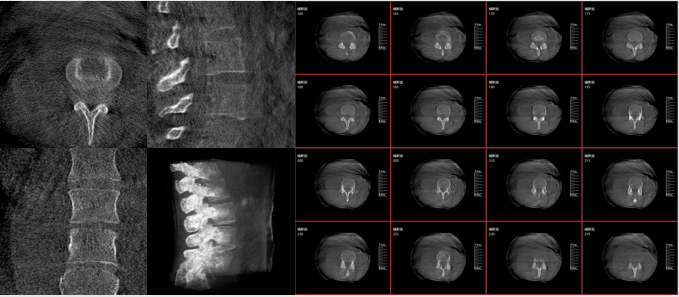

而三維影像的MPR圖像組可以通過不同平面的切分,使成像區(qū)內(nèi)更豐富的信息得以呈現(xiàn)。尤其是二維影像無法涉及的橫斷面,提供了另一個空間維度的信息量。

術(shù)中三維C臂影像